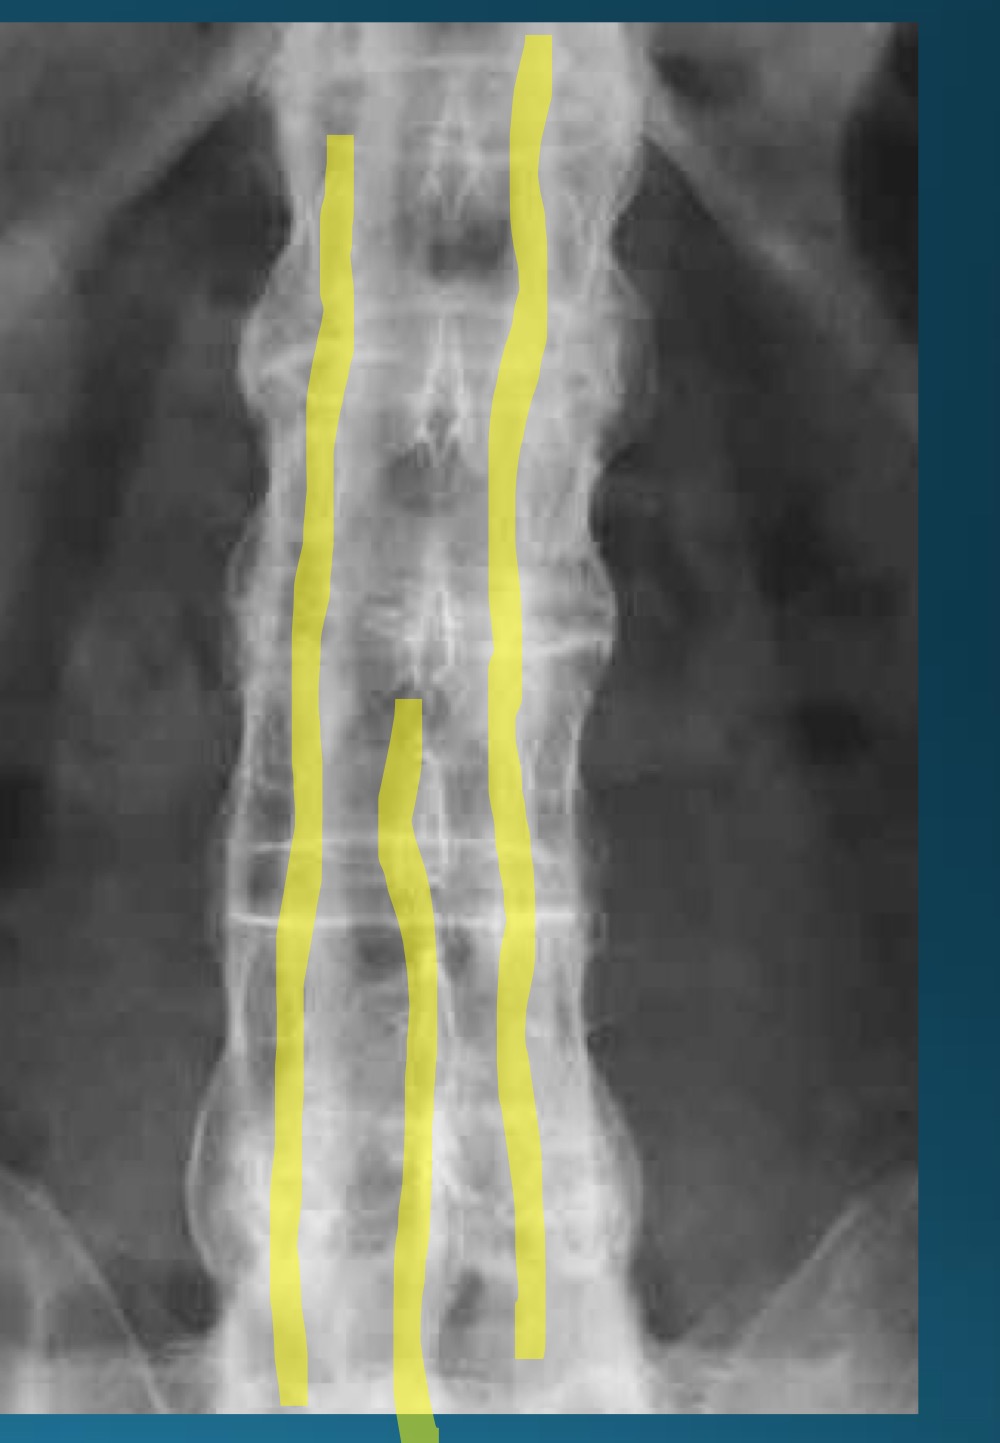

what do you call this sign? what diangosis is this apart of?

trolley track sign

AS